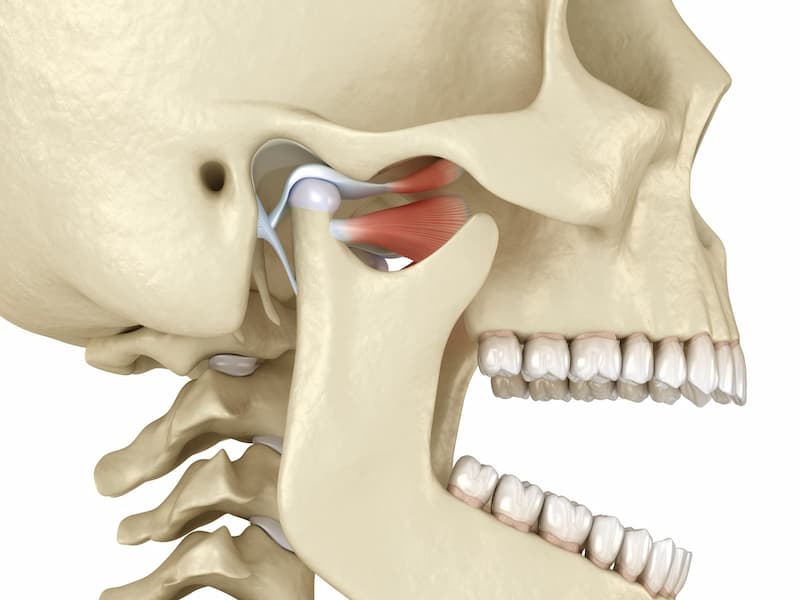

در واقع با استفاده از این روش می توان دندان مصنوعی قرار داد که معمولا با جراحی کردن نیز همراه است.